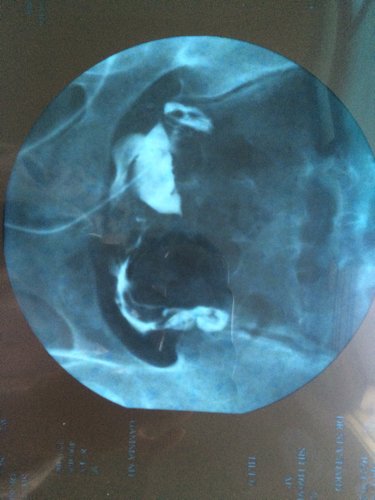

麻烦看看图,检查结果显示双侧输卵管通畅,但是医生看了片说通畅得不好,很难自然怀孕,要求做宫腔镜手术 麻烦看看图,检查结果显示双侧输卵管通畅,但是医生看了片说通畅得不好,很难自然怀孕,要求做宫腔镜手术,这什么情况呀? 点击展开 494317348 2015-05-01 18:51 为您推荐: 其他回答 通畅。建议在两次月经之间那几天爱爱比较容易受孕。还要检查男方是不是精子也正常才行。 匿名用户 2015-05-01 20:09 准备坑你钱了 匿名用户 2015-05-01 19:01 这是手术里面的 匿名用户 2015-05-01 18:52 相关问题 请问做宫腔镜检查都是好的!输卵管口也是清晰可见是不是说明输卵管也是通的?有图!麻烦懂的人帮忙分析一 怀孕五个月,发现右肾结石,医生建议保守治疗,建议多喝水自然排石,问题是如果长时间自然排石不成功对孕 我想问下医生如果子宫有炎症,怀孕了是不是查不出来,麻烦专业医生回答,谢谢